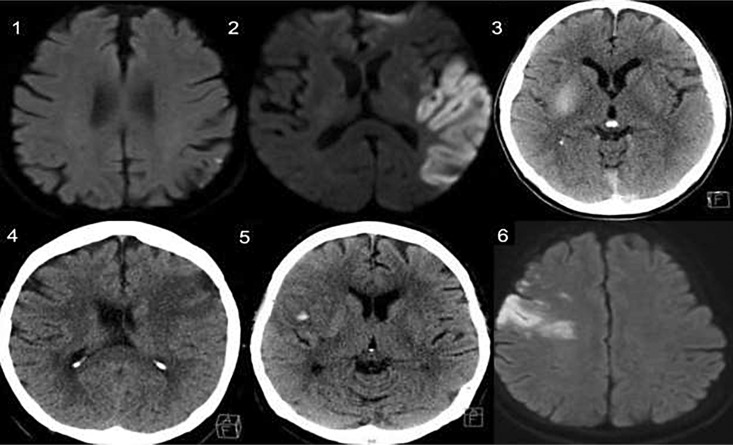

Abstract Image